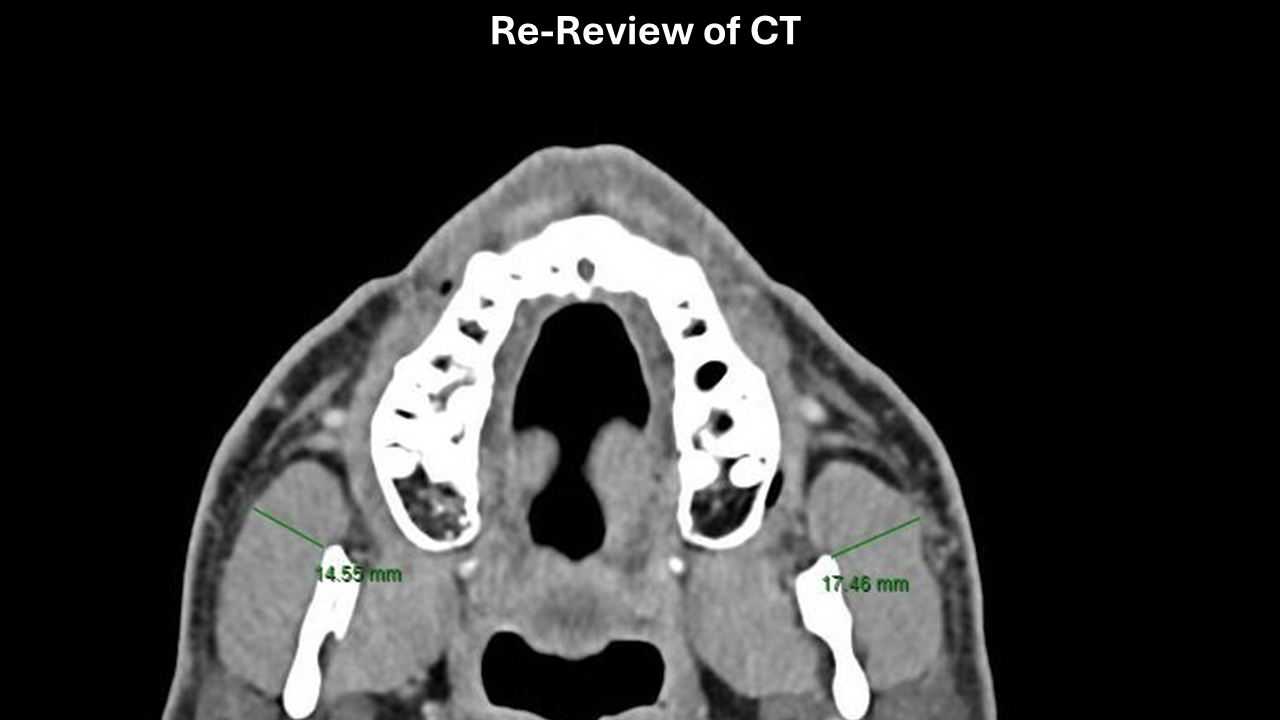

CT masseter enlargement